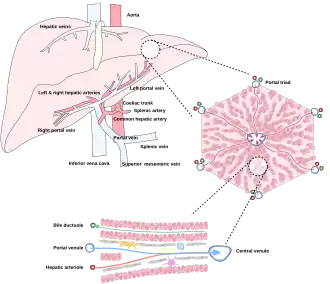

The liver is connected to two large blood vessels: the hepatic artery and the portal vein. The hepatic artery carries oxygen-rich blood from the aorta via the celiac trunk, whereas the portal vein carries blood rich in digested nutrients from the entire gastrointestinal tract and also from the spleen and pancreas.[11] These blood vessels subdivide into small capillaries known as liver sinusoids, which then lead to hepatic lobules.

Hepatic lobules are the functional units of the liver. Each lobule is made up of millions of hepatocytes, which are the basic metabolic cells. The lobules are held together by a fine, dense, irregular, fibroelastic connective tissue layer extending from the fibrous capsule covering the entire liver known as Glisson's capsule after British doctor Francis Glisson.[4] This tissue extends into the structure of the liver by accompanying the blood vessels, ducts, and nerves at the hepatic hilum. The whole surface of the liver, except for the bare area, is covered in a serous coat derived from the peritoneum, and this firmly adheres to the inner Glisson's capsule.

Microscopic anatomy

Cells, ducts, and blood vessels

Microscopically, each liver lobe is seen to be made up of hepatic lobules. The lobules are roughly hexagonal, and consist of plates of hepatocytes, and sinusoids radiating from a central vein towards an imaginary perimeter of interlobular portal triads.[24] The central vein joins to the hepatic vein to carry blood out from the liver. A distinctive component of a lobule is the portal triad, which can be found running along each of the lobule's corners. The portal triad consists of the hepatic artery, the portal vein, and the common bile duct.[25] The triad may be seen on a liver ultrasound, as a Mickey Mouse sign with the portal vein as the head, and the hepatic artery, and the common bile duct as the ears.[26]

Histology, the study of microscopic anatomy, shows two major types of liver cell: parenchymal cells and nonparenchymal cells. About 70–85% of the liver volume is occupied by parenchymal hepatocytes. Nonparenchymal cells constitute 40% of the total number of liver cells but only 6.5% of its volume.[27] The liver sinusoids are lined with two types of cell, sinusoidal endothelial cells, and phagocytic Kupffer cells.[28] Hepatic stellate cells are nonparenchymal cells found in the perisinusoidal space, between a sinusoid and a hepatocyte.[27] Additionally, intrahepatic lymphocytes are often present in the sinusoidal lumen.[27]